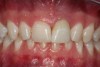

A young man presented with a fractured maxillary left-central incisor on a Monday morning after a Saturday evening discussion that did not end well (Figure 1). Visual oral examination and palpation of the structures revealed mobility of 3+, pain on palpation and percussion, a thick soft-tissue profile, and a low lip line. Gingival zeniths were irregular, there was a class II division 2 deep bite, and the periodontium was healthy overall (Figure 2 through Figure 4). Radiographs requested at the time of the initial visit were periapicals, panoramic, and CBCT images (Figure 5 and Figure 6). After all images and information were reviewed and the extent of his injury was discussed, the patient was presented with the following options: removable prosthetics, fixed partial denture, extract and do nothing, or extract and place a dental implant with bone augmentation.

Fig 2. Preoperative photograph after trauma.

Figure 2

Fig 3. Retracted photograph, teeth apart.

Figure 3

Fig 4. Retracted photograph, in occlusion.

Figure 4